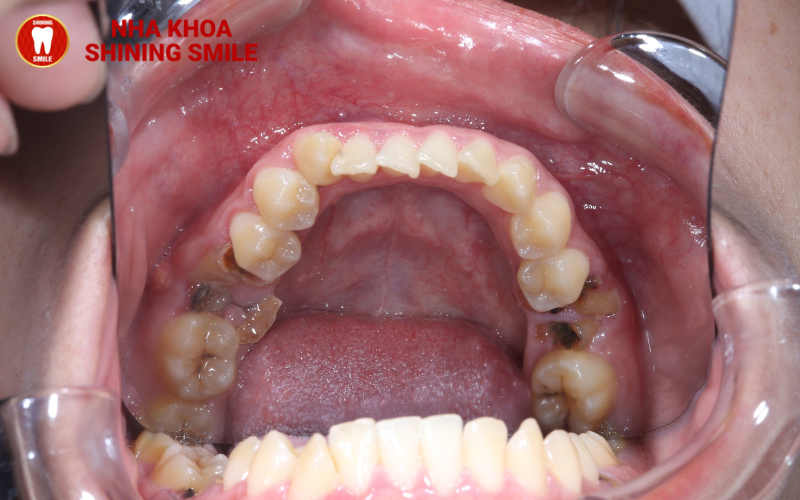

Răng số 6 bị sâu/ hư hỏng nặng sẽ cần phải nhổ bỏ

Khi được hỏi tại sao trong chỉnh nha niềng răng nhiều khách hàng cần phải kéo răng số 7 thay răng số 6 các nha sĩ cho rằng, chiếc răng ở vị trí số 6 khi đã hư hỏng quá nặng cần phải thay răng. Và đâu là những nguyên nhân khiến răng số 6 bị hư hỏng?

Răng số 6 thường bắt đầu mọc từ sớm, ở đuổi còn nhỏ việc ý thức chăm sóc sức khỏe răng miệng chưa tốt. Đó cũng chính là lý do răng số 6 rất dễ bị sâu, mòn men răng dễ bị hỏng sớm.

Răng số 6 nằm ở vị trí khuất bên trong hàm nên việc vệ sinh cũng khá khó khăn. Việc chải răng hằng ngày không kỹ, thức ăn, mảng bám lâu ngày trên kẽ răng cũng gây viêm nha chu và ảnh hưởng đến sức khỏe của vị trí răng này.

Một nguyên nhân khác đó chính là răng này đảm nhiệm chức năng ăn nhai, nghiền nát thức ăn chính trên cung hàm. Vì làm việc nhiều nên việc suy giảm “sức khỏe” và dễ gây hư hỏng cũng là điều dễ hiểu.